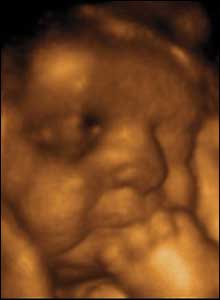

وهذه صور أجنة توأم عبر جهاز موجات فوق الصوتية :